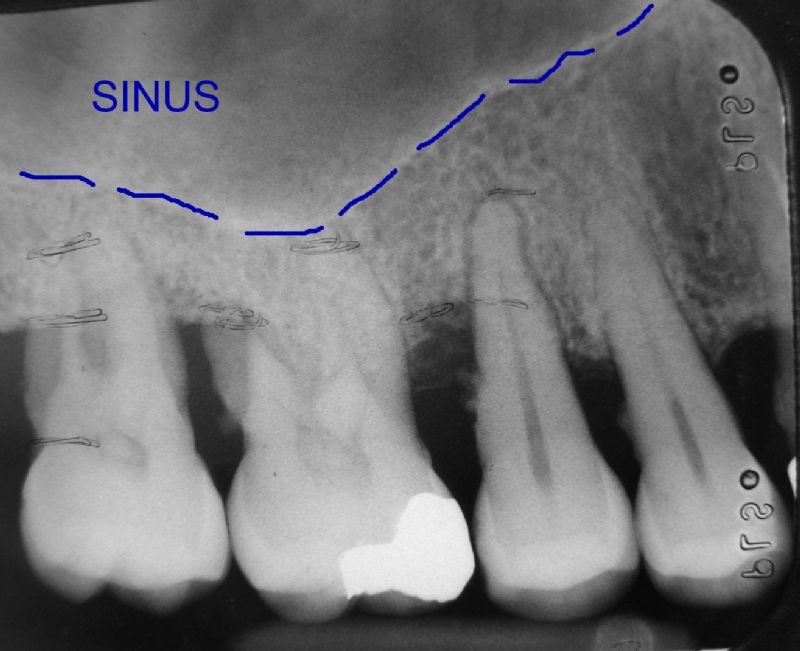

In the back part of the upper jaw, there is a large sinus (air space which is connected to the nasal (nose) space. Commonly, the floor of the sinus is very low, and close to the mouth, thus not leaving enough vertical height of bone into which dental implants can be placed to an adequate depth.

Here are the four back teeth before being removed. As a result of severe periodontal disease, there was insufficient bone to continue holding them, and they were extremely loose.